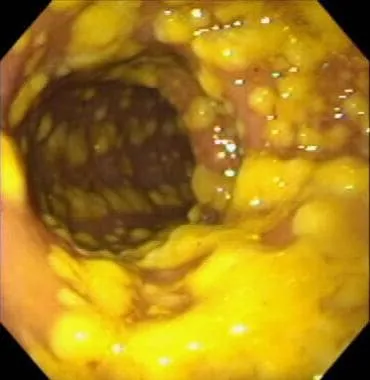

- Toxin A (enterotoxin) and Toxin B (cytotoxin) lead to mucosal injury, inflammation, and formation of pseudomembranes.

- Results in profuse, watery diarrhea, abdominal cramping, and potential toxic megacolon.